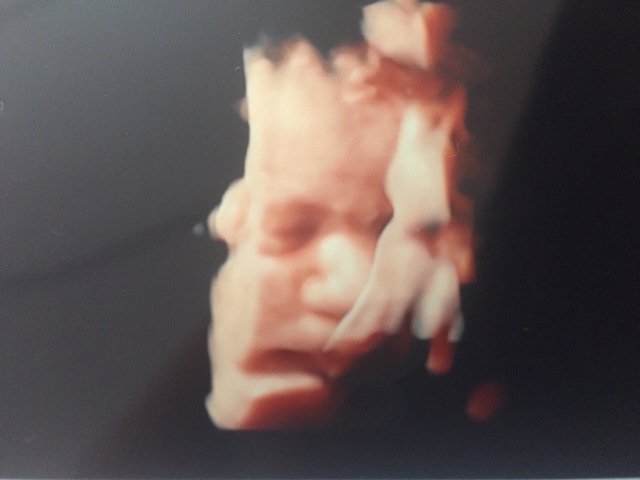

毎回3D.4Dで見るのを楽しみにしていたのですが、なかなか顔を見せてくれず妊娠中に4Dができたのは2回だけでした^_^!

最後は37週の時だったのですが、産まれてきてからの顔と比べて見るとそっくりでした!